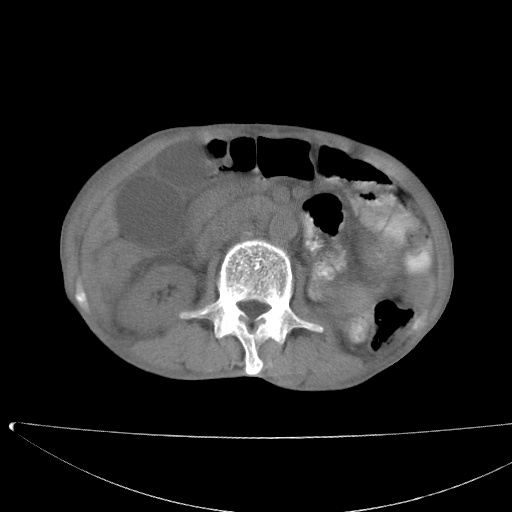

标题: CT17147:男70岁,上腹部不适1月。 [打印本页]

患者男70岁,上腹部不适1月。8年前有胃癌手术史。余病史不祥。

1、胃癌根治胃空肠吻合术后,残胃癌?

2、肝门区占位性病变并胆道上段梗阻(肝内胆管扩张、胆囊增大),考虑肝门区淋巴结转移累及胆总管,建议ct增强扫描;

3、右侧胸腔少量积液、少量腹水;

4、肝右叶胆管结石。